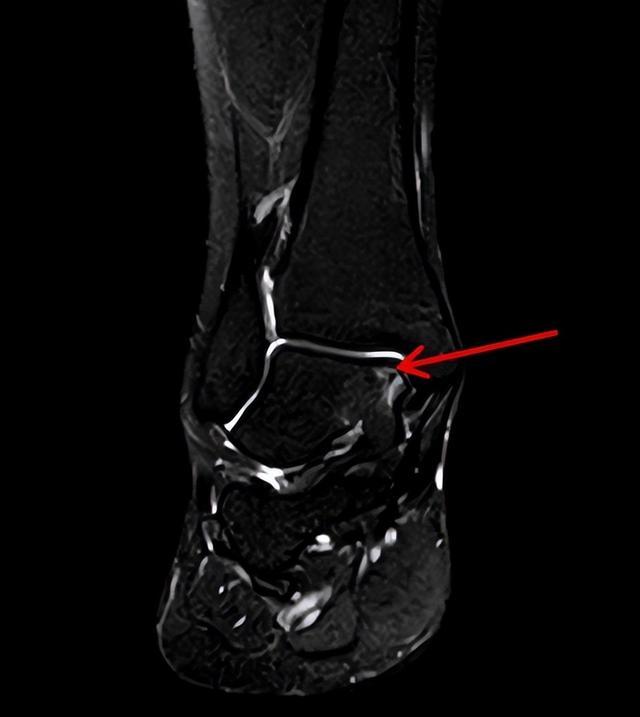

2023年8月6日,她经人介绍来到湖南省人民医院骨关节与运动医学科王靖主任医师处就诊,核磁共振检查显示:右侧踝关节内侧距骨软骨损伤,随即因“右踝距骨剥脱性骨软骨炎”将她收入关节与运动医学科病房。

▲术前MRI可见:距骨软骨损伤,软骨下骨碎片分离